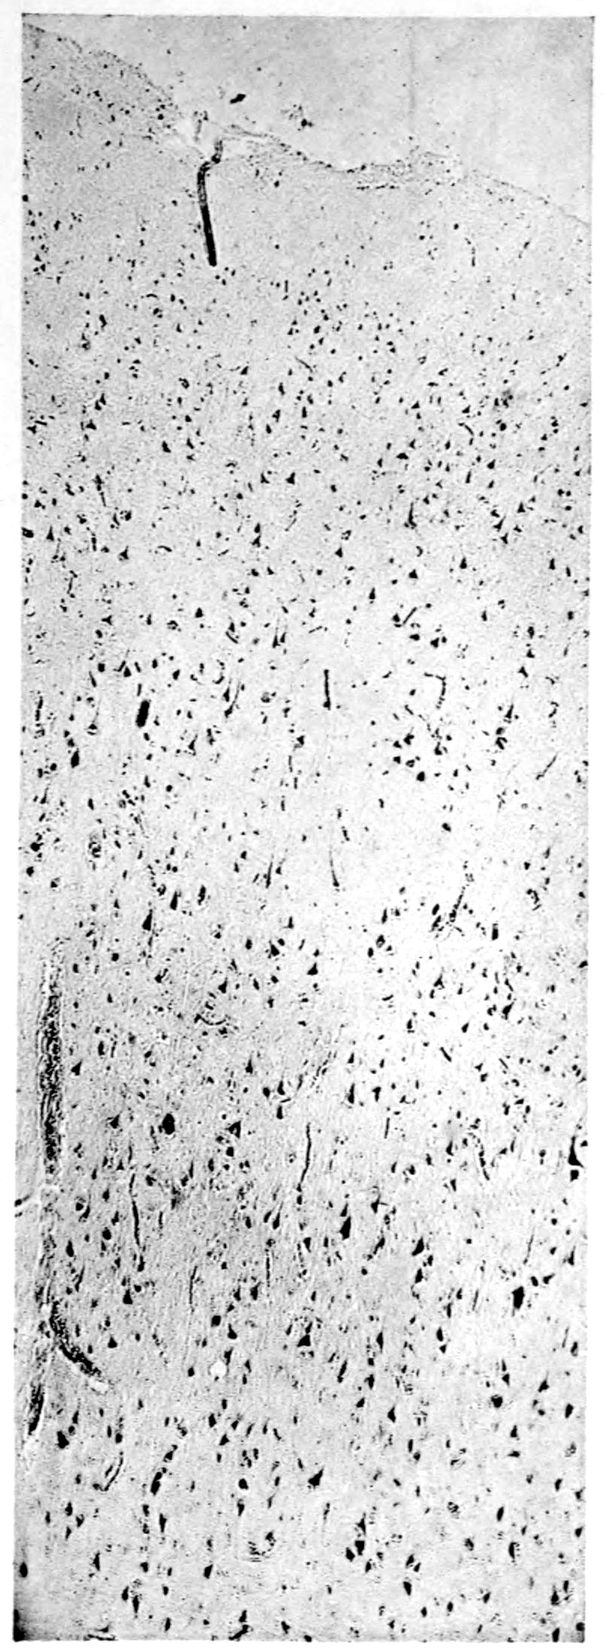

A. Normal postcentral cortex. (Compare B.)

B. Nerve cell losses. Perivascular deposits of mononuclear cells, amongst which are numerous plasma cells. Note decrease in number of nerve cells. Note irregular disposition of nerve cells. From paretic neurosyphilis.

Apparent new formation of small blood vessel. Photographed by Dr. A. M. Barrett.

Rod cells (Stäbchenzellen) in paretic neurosyphilis. Photographed by Dr. A. M. Barrett.

Granular ependymitis—microscopic appearance of a marked example of “sanding” of ventricle.

41Characteristic and constant in paretic neurosyphilis is the Plasmocytosis and Lymphocytosis, Perivascular in distribution about small cortical vessels. There is also a characteristic (though characteristically less prominent) Plasmocytosis and Lymphocytosis, Meningeal in distribution. The pleocytosis of the spinal fluid, almost constant though variable in amount in life, is an indicator of the meningeal picture and less directly of the parenchymatous picture.

Granular Ependymitis (“sanding” of ventricle floors) is characteristic and may be regarded as part of the parenchymatous picture. This ependymitis is an indicator how chemical changes could be readily produced at least in the ventricular fluids, since the limiting membranes of the nerve tissue are here subject to multiple breaks. The “sanding” is a neuroglia reaction to these multiple small breaks (Weigert’s explanation).